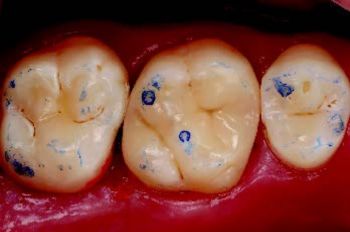

Etter isolering med kofferdam og pre-kiling ble den gamle restaureringen fjernet med diamantbor under vannkjøling. Kaviteten ble renset og behandlet med 27 μm aluminiumoksid via luftabrasjon. Siden kuspene var >2 mm, var kuspedekke unødvendig (Fig. 2).

Figur 2: Ferdig kavitet etter partikkelbasert luftabrasjon.